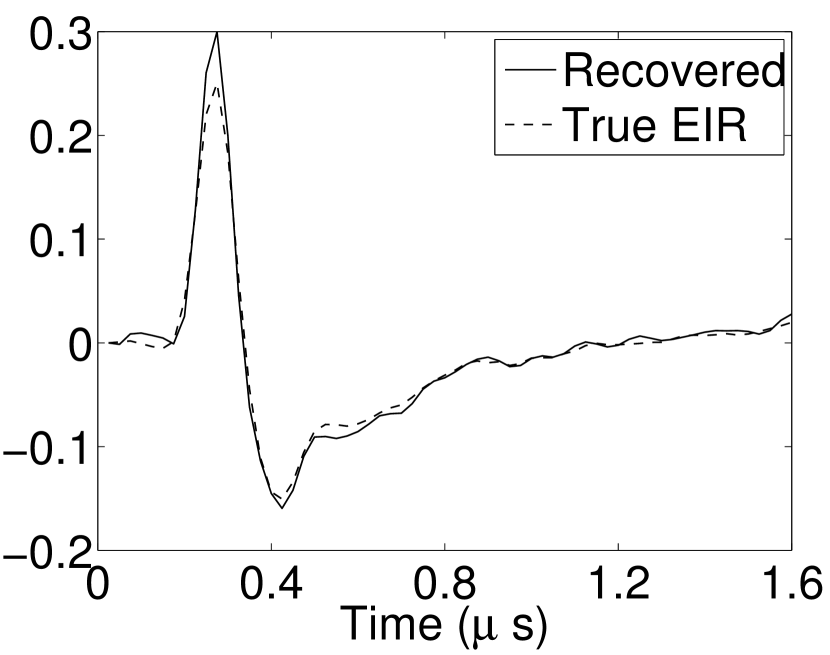

A 2D circular measurement geometry was employed. transducers were evenly distributed on a ring of radius mm that enclosed the phantom. The SOS was assumed to be constant and set at mm/s. Since the simulated data were formed by use of the C-D imaging model in Eqn. (2), no inverse crime was committed. The components of this vector corresponded to equally spaced temporal samples over the interval s. Subsequently, the noiseless voltage vector was obtained by convolving the pressure data with EIR-1 in Figure 1(b).

Each element in a real-world transducer array possesses its own EIR. In practice, the differences between the EIRs are sometimes neglected and an EIR corresponding to a single element may be used to represent all elements in the array. In some of the studies below, the EIR employed to initialize the VP algorithm (EIR-2 in Figure 1(b)) and the EIR employed to produce the simulated measurements (EIR-1 in Figure 1(b)) were experimentally measured from two different transducer elements in a circular transducer array (see Sec. VI-B). EIR-1 was measured by temporally integrating the PA signal produced by a point source positioned at the focus of the transducer. EIR-2 was measured by use of the method reported in [RNR2011]. In order to investigate the sensitivity of the VP algorithm to the initialization of the EIR, we employed different EIRs obtained by degrading EIR-1 as described later. When solving the sub-problem in Line-2 of Algorithm 1, was initialized as the zero vector. Algorithm 1 was terminated after 500 iterations, since it was observed that the changes in the reconstructed images with more iterations were negligible. When implemented by use of a single core of an Intel Xeon E5-2640 CPU, each iteration required approximately 7s to complete.

Figure 7(a) reveals that use of the inaccurate EIR in the conventional iterative method created strong artifacts and distortions. Figures 7(b) confirms that the artifacts and distortions were significantly mitigated when the VP method was employed. Image profiles for both cases are shown in Figures 7(c). The overall accuracy of the recovered EIR, shown in Figure 7(d) and 7(e), was improved, but it contained spurious oscillations.